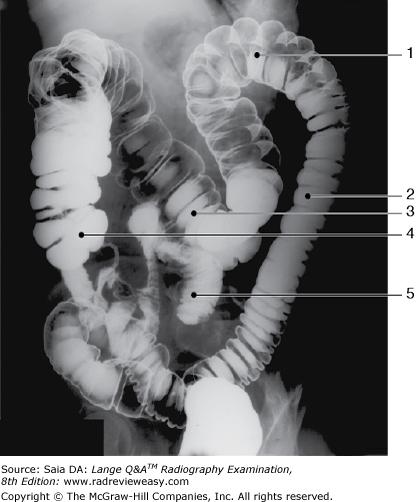

The structure indicated by the number 2 in Figure 6–11 is the

B descending colon.

-The figure shown is a double-contrast BE, oblique position. Since the left colic/splenic flexure (number 1) is “open,” this is either a RPO or LAO position. Also demonstrated are the descending colon (number 2), and transverse colon (number 3). Barium has refluxed into the ileum (number 5).

In which of the following positions was the radiograph in Figure A taken?

B LPO

-The pictured radiograph is an oblique position of the large bowel, illustrating an "open" view of the hepatic/right colic flexure and ascending colon, with the splenic/left colic flexure superimposed on the descending colon. Therefore, the radiograph must have been made in either an RAO (if the patient was prone) or an LPO (if the patient was supine) position. The LAO and RPO positions are used to demonstrate the splenic/left colic flexure and descending colon free of self-superimposition. AP or PA axial is generally used to visualize the rectosigmoid colon.